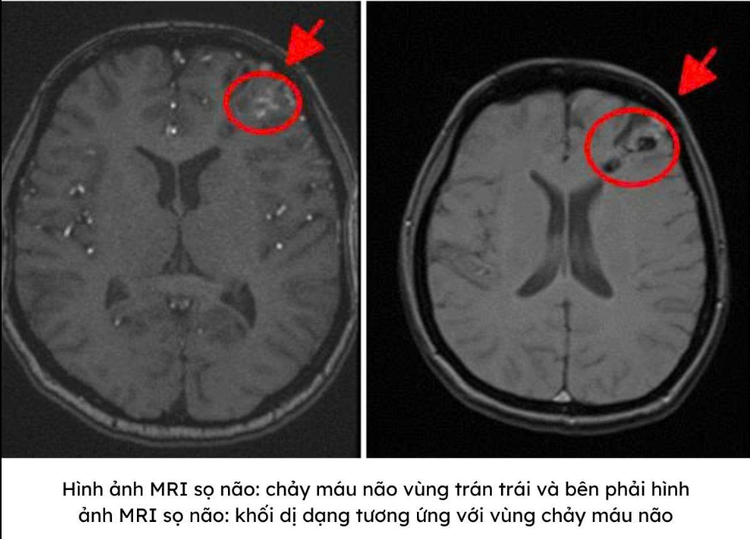

Để xác định chính xác nguyên nhân, bác sĩ chỉ định chụp MRI 3.0 Tesla. Kết quả cho thấy đúng như dự đoán, người bệnh có ổ chảy máu tại thùy trán trái, do vỡ dị dạng động, tĩnh mạch não – một dạng “mạch máu nối sai cách”, nơi động mạch nối trực tiếp vào tĩnh mạch mà không qua hệ mao mạch đệm.

Trong ổ dị dạng còn xuất hiện một túi phình nhỏ, điểm yếu rất dễ vỡ lại nếu không được can thiệp kịp thời. Toàn bộ cấu trúc bất thường này giống như một “ổ mạch máu rối”, nơi dòng máu chảy với áp lực cao khiến thành mạch mỏng yếu và dễ gây chảy máu vào não.